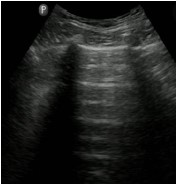

Assinale a opção que apresenta a imagem de ultrassonografia pulmonar compatível com a descrição do quadro acima.